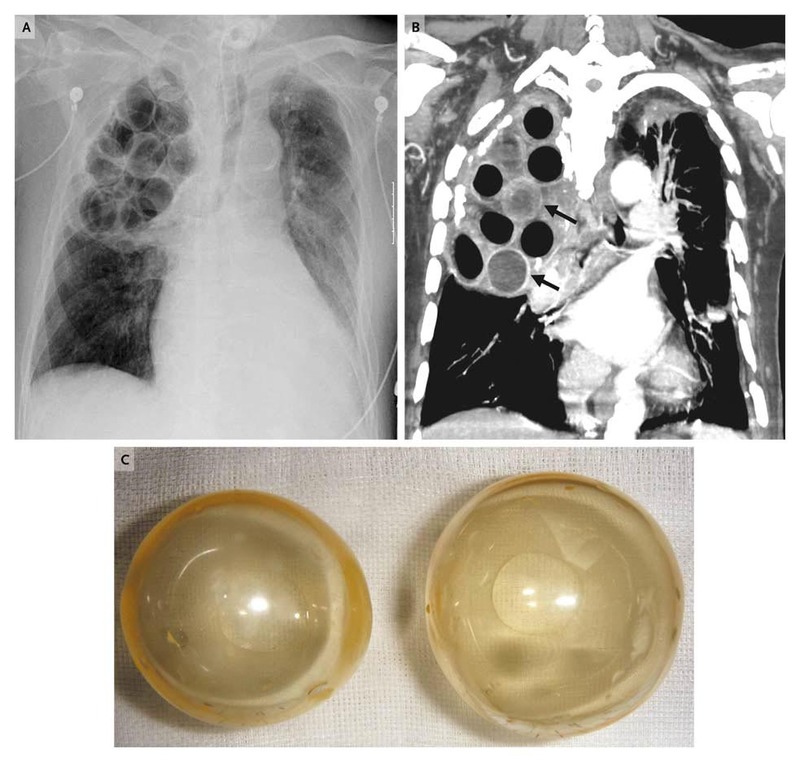

Plombage

Open in gallery (11)

Plombage.

Plombage.Source: Journal of Medicine

Plombage was a risky treatment for tuberculosis, in which the surgeon created a cavity in the upper part of the patient's chest wall. To make the lung collapse, a hole was drilled between the patient's ribs and the space was filled with various materials - ping pong balls, oil, rubber sheeting or gauze. The theory was that a collapsed lung would eventually heal itself. Of course, the treatment was not without side effects.